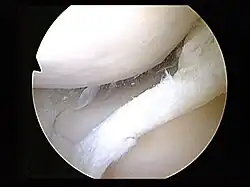

Surgery

Arthroscopy is a surgical technique in which a joint is operated on using an endoscopic camera as opposed to open surgery on the joint. The meniscus can either be repaired or completely removed.[20] Surgery is not appropriate for a degenerative meniscus tear, absent locking or catching of the knee, recurrent effusion or persistent pain.[25] Evidence suggests that it is no better than conservative management in those with and without osteoarthritis.[31][32] Surgery appears to offer no benefit to adults who have mild arthritis.[32]